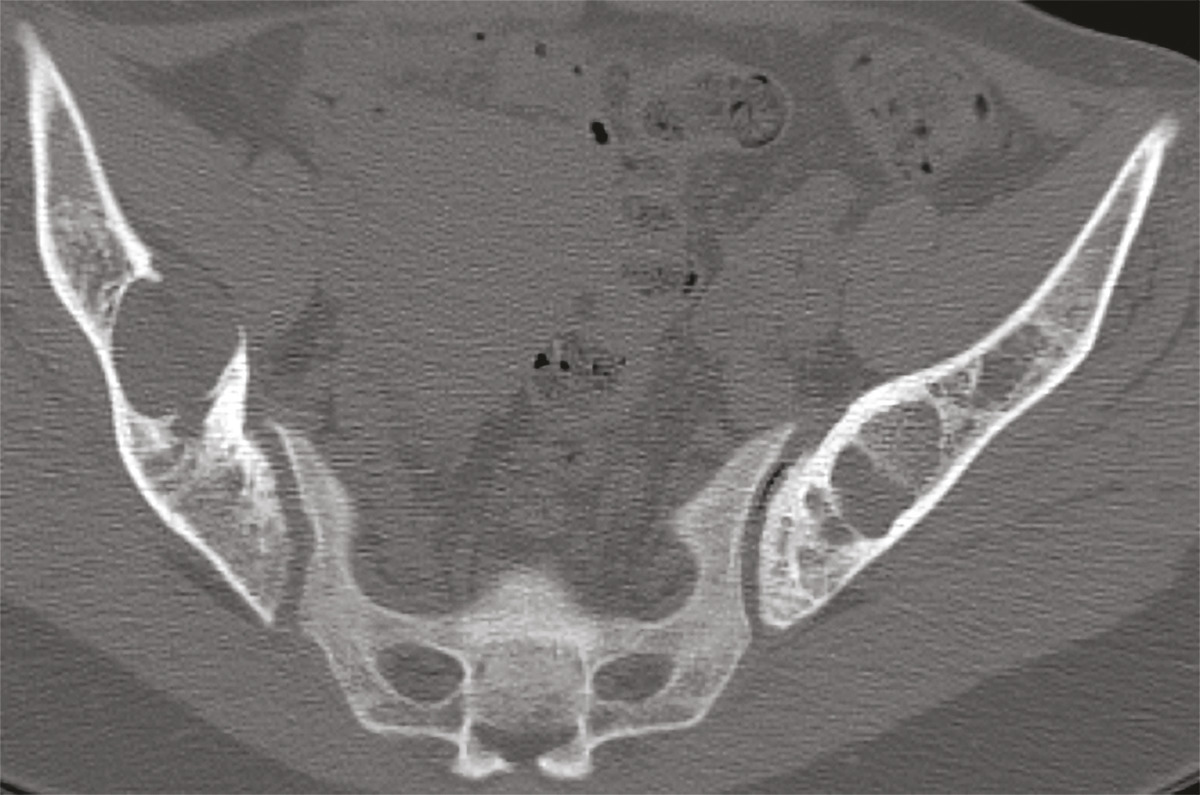

Cette femme de 31 ans sans antécédents était adressée pour des douleurs pelviennes, un syndrome polyuro-polydipsique et une altération de l’état général. Le bilan biologique montrait une hypercalcémie, une hypophosphorémie, une hypovitaminose D et une hyperparathormonémie. La tomodensitométrie (TDM) [fig. 1 ] et l’imagerie par résonance magnétique (IRM) [fig. 2 ] du pelvis révélaient un aspect ostéolytique diffus avec des nodules tumoraux des ailes iliaques. La scintigraphie et l’examen histologique de trois volumineuses glandes parathyroïdes permettait de retenir le diagnostic d’hyperplasie parathyroïdienne primaire. La biopsie osseuse confirmait le diagnostic de tumeurs brunes osseuses associées à l’hyperparathyroïdie. L’évolution était favorable sous traitement symptomatique et antalgique.